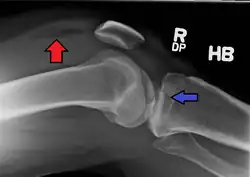

Lipohemarthrosis (presence of fat and blood from bone marrow in the joint space after an intraarticular fracture) seen on X-ray in a person with a subtle tibial plateau fracture

Lipohemarthrosis due to a tibial plateau fracture

Subtle tibial plateau fracture on an AP X ray of the knee

A tibial plateau fracture seen on X-ray